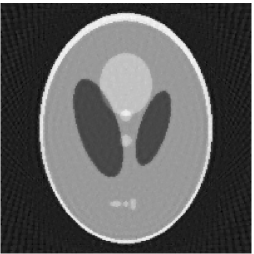

Noiseless projection data: The projection data were collected by calculating line integrals across the phantom at 60, 90, 120 directions(equal increments and from to ) of 201 equally spaced parallel lines from to . Iteration procedures were terminated when for the noiseless experiments.

The reconstruction images from the noiseless projection data were shown in the Fig. 2. From Fig. 2, we can observe that the classic and the proposed algorithms can reconstruct images from the three projection data. In order to show the advantages of the proposed algorithm visually, the central vertical line of the differences between the reconstructed images and the original image are present in Fig. 3. We can observe that the -PP superiorization is more efficient than the classic superiorization in the aspect of suppressing the artifacts in the reconstructed images.

In order to compare the images in Fig. 2 quantitatively, we tabulated the iterations, MSE, Res and running time(RT) of programs in Table 1. By comparing the numbers in Table 1, we can draw the conclusion that the proposed method can improve the quality of the estimated images and save computation time.

In order to compare the convergent speed of the proposed algorithms with the classic algorithms visually, we present the evolution of MSE along with the iteration process in Fig. 4 for the 3 projection data. And we can observe that the proposed perturbation can accelerate the convergent rate and improve the reconstructed image qualities.